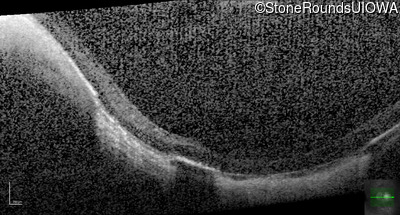

Optical Coherence Tomography - Right - 10/180

Exemplar / OCT Stack

Optical Coherence Tomography - Left - 20/40